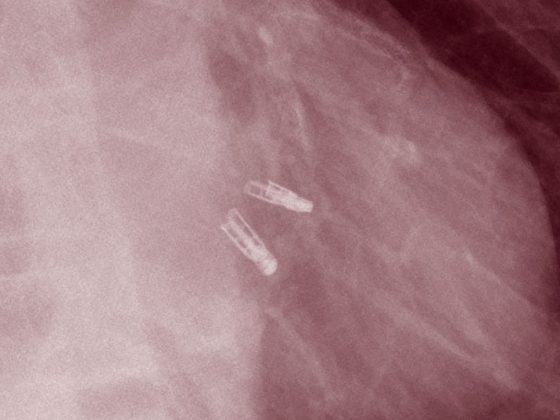

mitraclips

• Interventionelle Therapieverfahren

Fokus funktionelle Mitralklappeninsuffizienz

• Chirurgie

• Kardiologie

• Kongressberichte

• Rx

• Studien

Weiterlesen